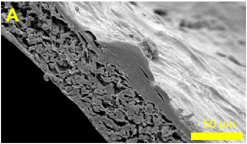

Skin cells growing on a polymer scaffold ...

© University of Sheffield

Tissue Engineering

Scientists are turning to chemistry and engineering to develop a range of artificial skin and bone which can be used to improve the treatment of burns and bone diseases.

Tissues are being grown by using complex man made 'scaffolds' to support them – not unlike scaffolding on a house - these scaffolds are not made from steel but of bio-ceramics and plastic polymers.